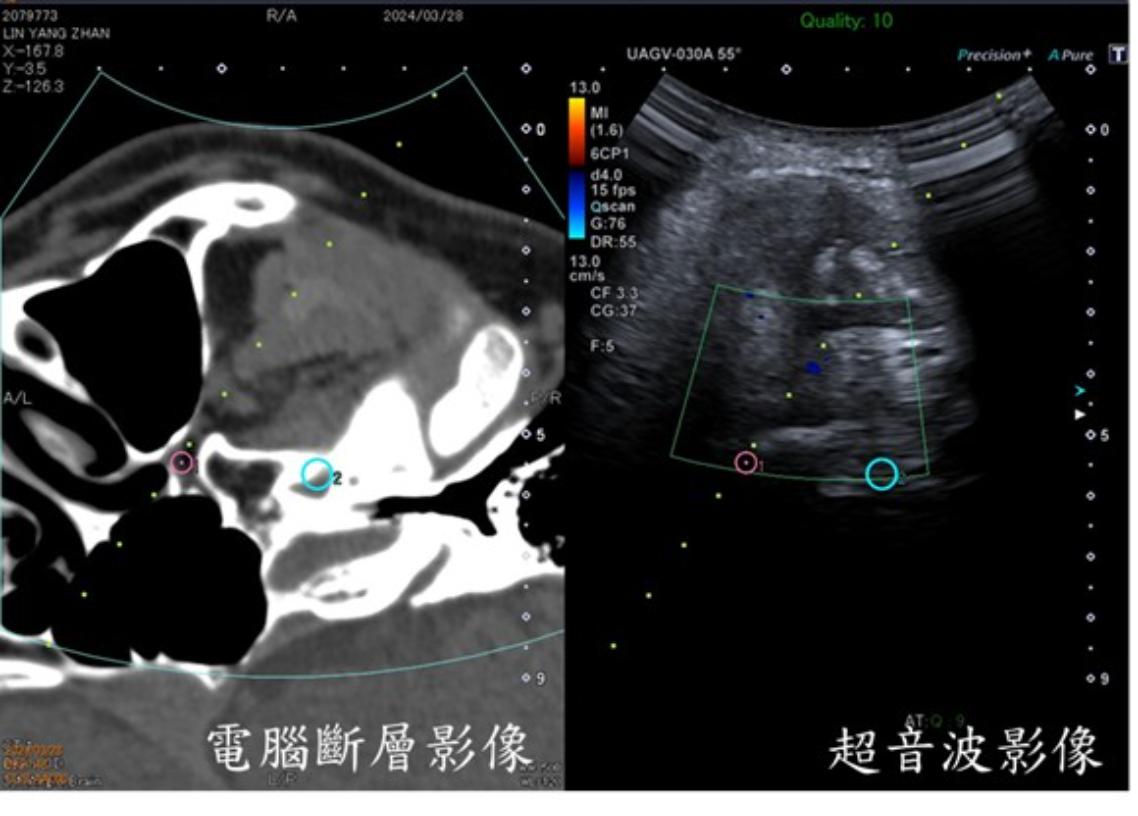

許一智解釋,首先會在病患頭部貼上磁導裝置,接著進行顱底CT掃描,以取得神經孔與周邊結構的精準影像,隨後將這些CT影像匯入超音波儀器中。當醫師把超音波探頭放在患者臉部並按下同步鍵後,超音波畫面便會即時顯示CT影像,兩者以一對一的方式同步呈現,醫師因此能同時看見即時的血管與軟組織位置,以及CT所呈現的骨性神經孔結構。

藉由這種融合影像,醫師能在畫面上直接標示目標神經孔(例如圓孔、卵圓孔),讓針尖得以沿著最佳、安全的路徑前進至治療位置。